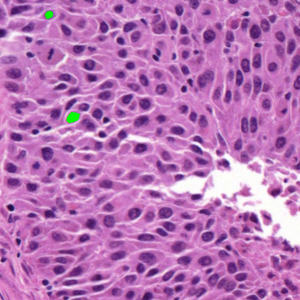

Dataset 2, released as supplementary material in [73], contains 36 digitized H&E-stained microscopy images (600 × 600 pixels) with 7931 nuclei annotated by three expert pathologists; only consensus annotations are retained. It is designed for cell nuclei detection.

Representative samples from the three datasets are shown in Fig. 1. In (a), the first frame of the synthetic video in Dataset 1 illustrates the strong illumination gradients produced by distance-dependent shading together with orientation-dependent interactions between vertex normals and the light direction. The H&E images in (b) and (c), also from Dataset 1, depict a mast cell infiltrate from a patient with non-alcoholic steatohepatitis and cirrhosis and, respectively, a sample from a patient with sclerosing polycystic adenosis of the parotid gland; the former consists primarily of purple nuclei, white cytoplasm, and pink extracellular tissue. Subfigures (d) and (e) show two examples from Dataset 2 accompanied by their ground-truth nuclei annotations, while (f) and (g) present a representative image from Dataset 3 together with its corresponding cell mask.

Figure 1: Samples from Datasets 1–3. (a) First frame of the 74-frame video in Dataset 1 (1770 × 880) with a superimposed red mesh. (b,c) H&E-stained tissue images from Dataset 1 (1000 × 750; 950 × 730). (d,e) Cell images from Dataset 2 (600 × 600) with nuclei annotations. (f,g) Image from Dataset 3 (512 × 512) with annotation.